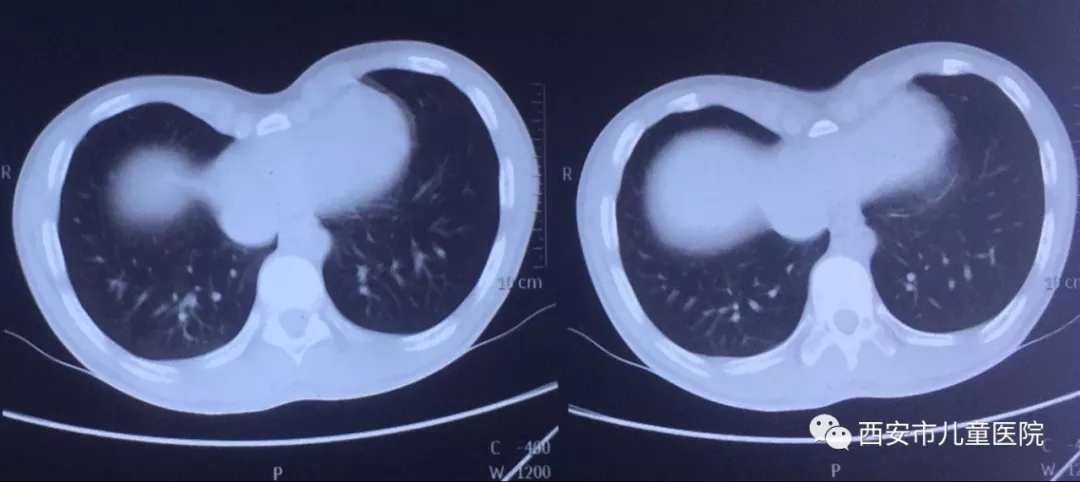

经过入院检查,这个15岁大男孩CT指数:4.0,不对称,胸廓骨质僵硬,家庭情况一般,15岁男孩是我院目前手术年龄最大患儿,更何况孩子为超重度、不对称漏斗胸,整个胸廓骨质僵硬,结合家庭情况,怎样能用一个漏斗胸支撑板解决以上问题,是目前急需要解决的问题。